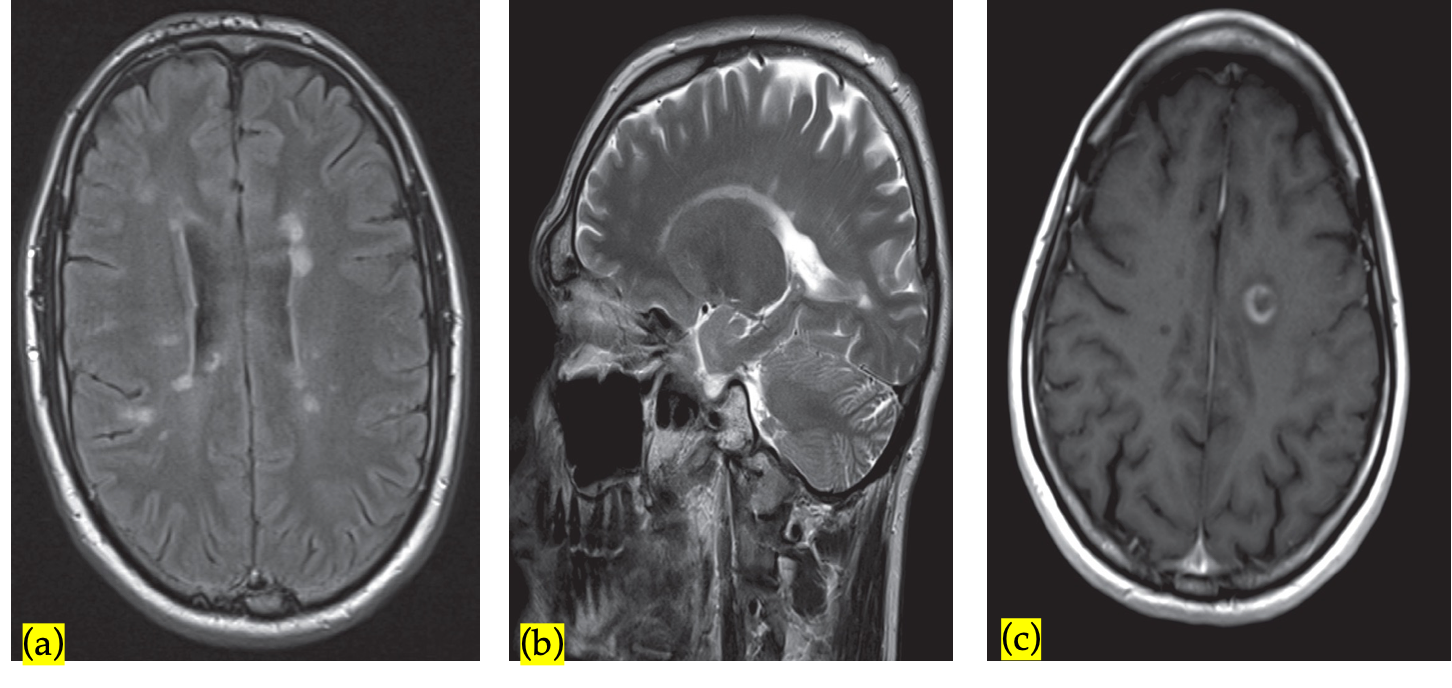

Spinal cord may be the earliest affected by MS plaques.

MRI spinal cord (with and without gadolinium):

To increase diagnostic yield (e.g., in patients with nondiagnostic brain MRI or symptoms of partial myelitis.

The most common finding on T2WI of one or more elongated, poorly marginated, hyperintense intramedullary lesions.

The foci may has mass effect and enhance at the post-contrast study.

A) T2-weighted MRI showing a plaque of demyelination (arrow) in a patient with multiple sclerosis

B) Multiple sclerosis - T2-weighted sagittal MRI of the spinal cord paramedian level: evidence of a hyperintensity of the spinal cord at the level of C4.